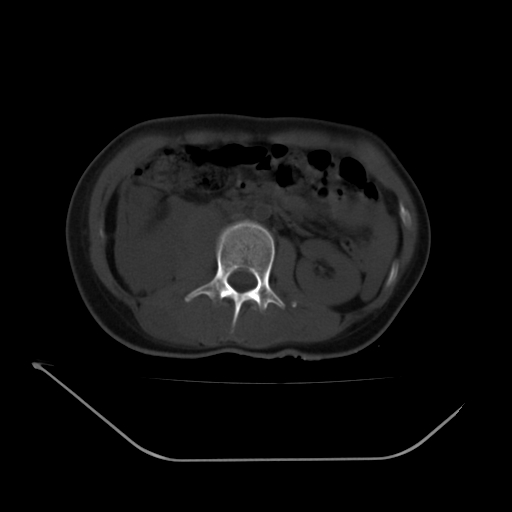

以下是引用liuyue在2008-7-19 13:02:00的发言:[br]1.肝右叶后下段及右肾挫裂伤伴腹腔积血。[br]2.右侧多发性肋骨骨折、横突骨折、右髂骨骨折伴周围软组织挫伤。[br]3.右侧腰大肌肿胀,并可见低密度影,如为气体,则肠道挫裂伤待除外。

以下是引用zhengfaming在2008-7-19 14:42:00的发言:[br]1.肝右叶后下段及右肾挫裂伤伴腹腔积血。脾脏挫裂伤待排[br]2.右侧多发性肋骨骨折、横突骨折、右髂骨骨折伴周围软组织挫伤。[br]3.右侧腰大肌肿胀,并可见低密度影,如为气体,则肠道挫裂伤待除外